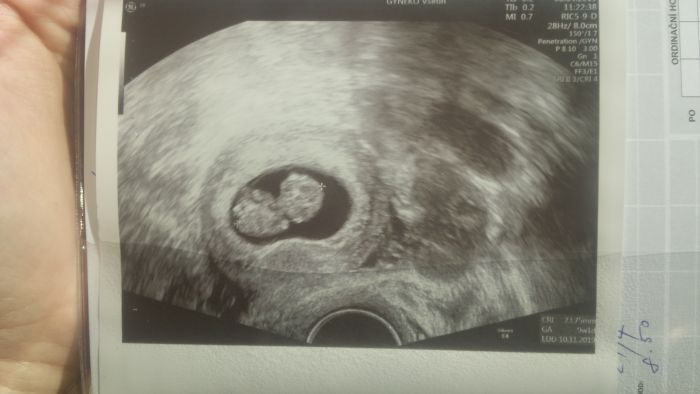

Ahoj holkySmile tak my máme termín podle PM 8.11.Smile V pondělí odběry, 29.4. Screening tak snad bude vše v pořádku jako doteď :)) snažili jsme se 3 roky..